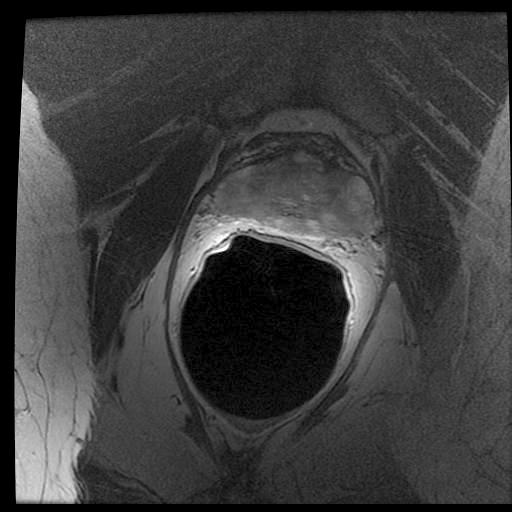

In the previous section, we simulated images in order to exploit “perfect segments”. In this section, we validate our approach using actual MR images of prostates. The image data from 15 patients were manually delineated by 5 oncologists.

The MR images used in this study were derived from an online database444http://prostatemrimagedatabase.com/. The database contains T2-weighted MR volume datasets, provided by Brigham and Women’s Hospital, the National Center for Image-guided Therapy, and Harvard Medical School. The images comprised T2-weighted MR images (T2W-MR) with endorectal coils. The pulse-sequence groups in the DICOM headers of most of the T2-weighted images were marked fast-spin echo (FSE), although some were marked as fast-relaxation fast-spin echo-accelerated (FRFSE-XL). The dataset contained images with slice thickness ranging from 2.5mm to 4.0mm, and varying contrast levels and signal-to-noise characteristics. All of the images were captured at a depth of 16 bits, and they varied in size from 256×\times256 to 512×\times512 pixels.

Sample images are depicted in Figure 6 (top row). Generally, one assumes that prostate segmentation is a relatively easy task. However, the variability of such segmentation remains considerable, and this is conspicuous in Figure 6 (bottom row).

Figure 6: Top: Sample MRI slices from different patients. Bottom: considerable variability among 5 oncologists.